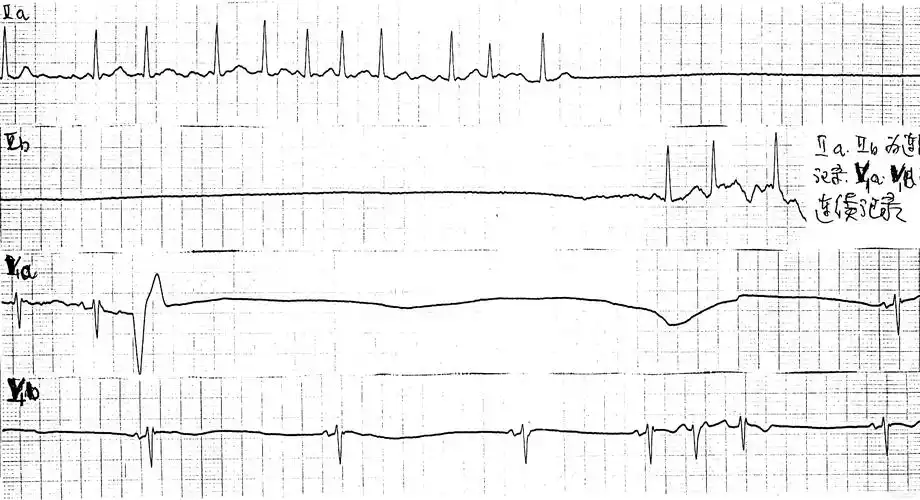

求:心电机械分离 和心室静止 的心电图图形